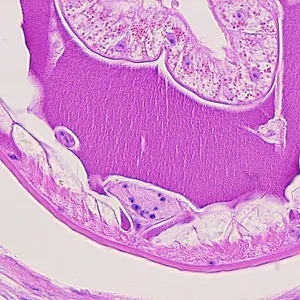

Case #215 – November, 2007

Figure A

This case was kindly contributed by the Laboratory of Parasitology, National Public Health Research Center in Vilnius, Lithuania.